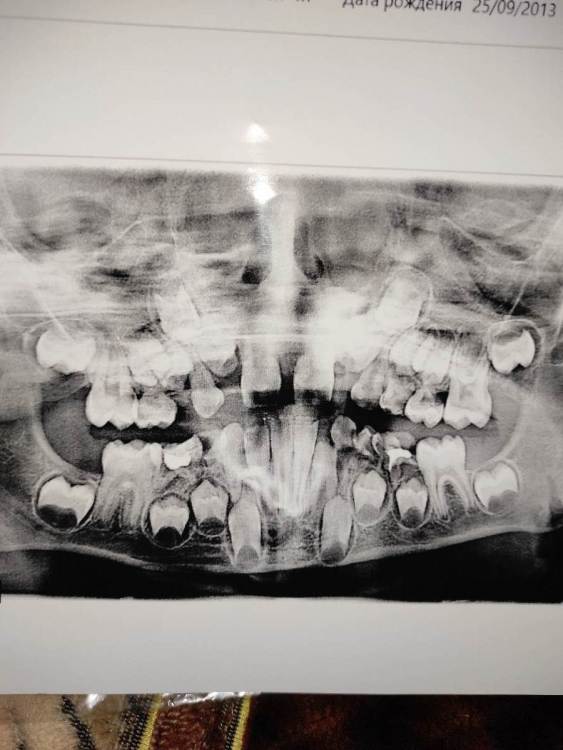

anna.yusupova.91 Опубликовано 19 сентября, 2021 Поделиться Опубликовано 19 сентября, 2021 Добрый день, подскажите пожалуйста у ребенку скоро 8 лет вот такие щели между зубами ,что надо делать?это как то попровимо? Ссылка на комментарий

St. Опубликовано 19 сентября, 2021 Поделиться Опубликовано 19 сентября, 2021 Добрый день. Во время роста челюсти и смены зубов с молочных на постоянные промежутки между зубами являются нормой. В плановом порядке покажитесь детскому или ортодонту. И обязательно тщательно следите за гигиеной дома! Ссылка на комментарий